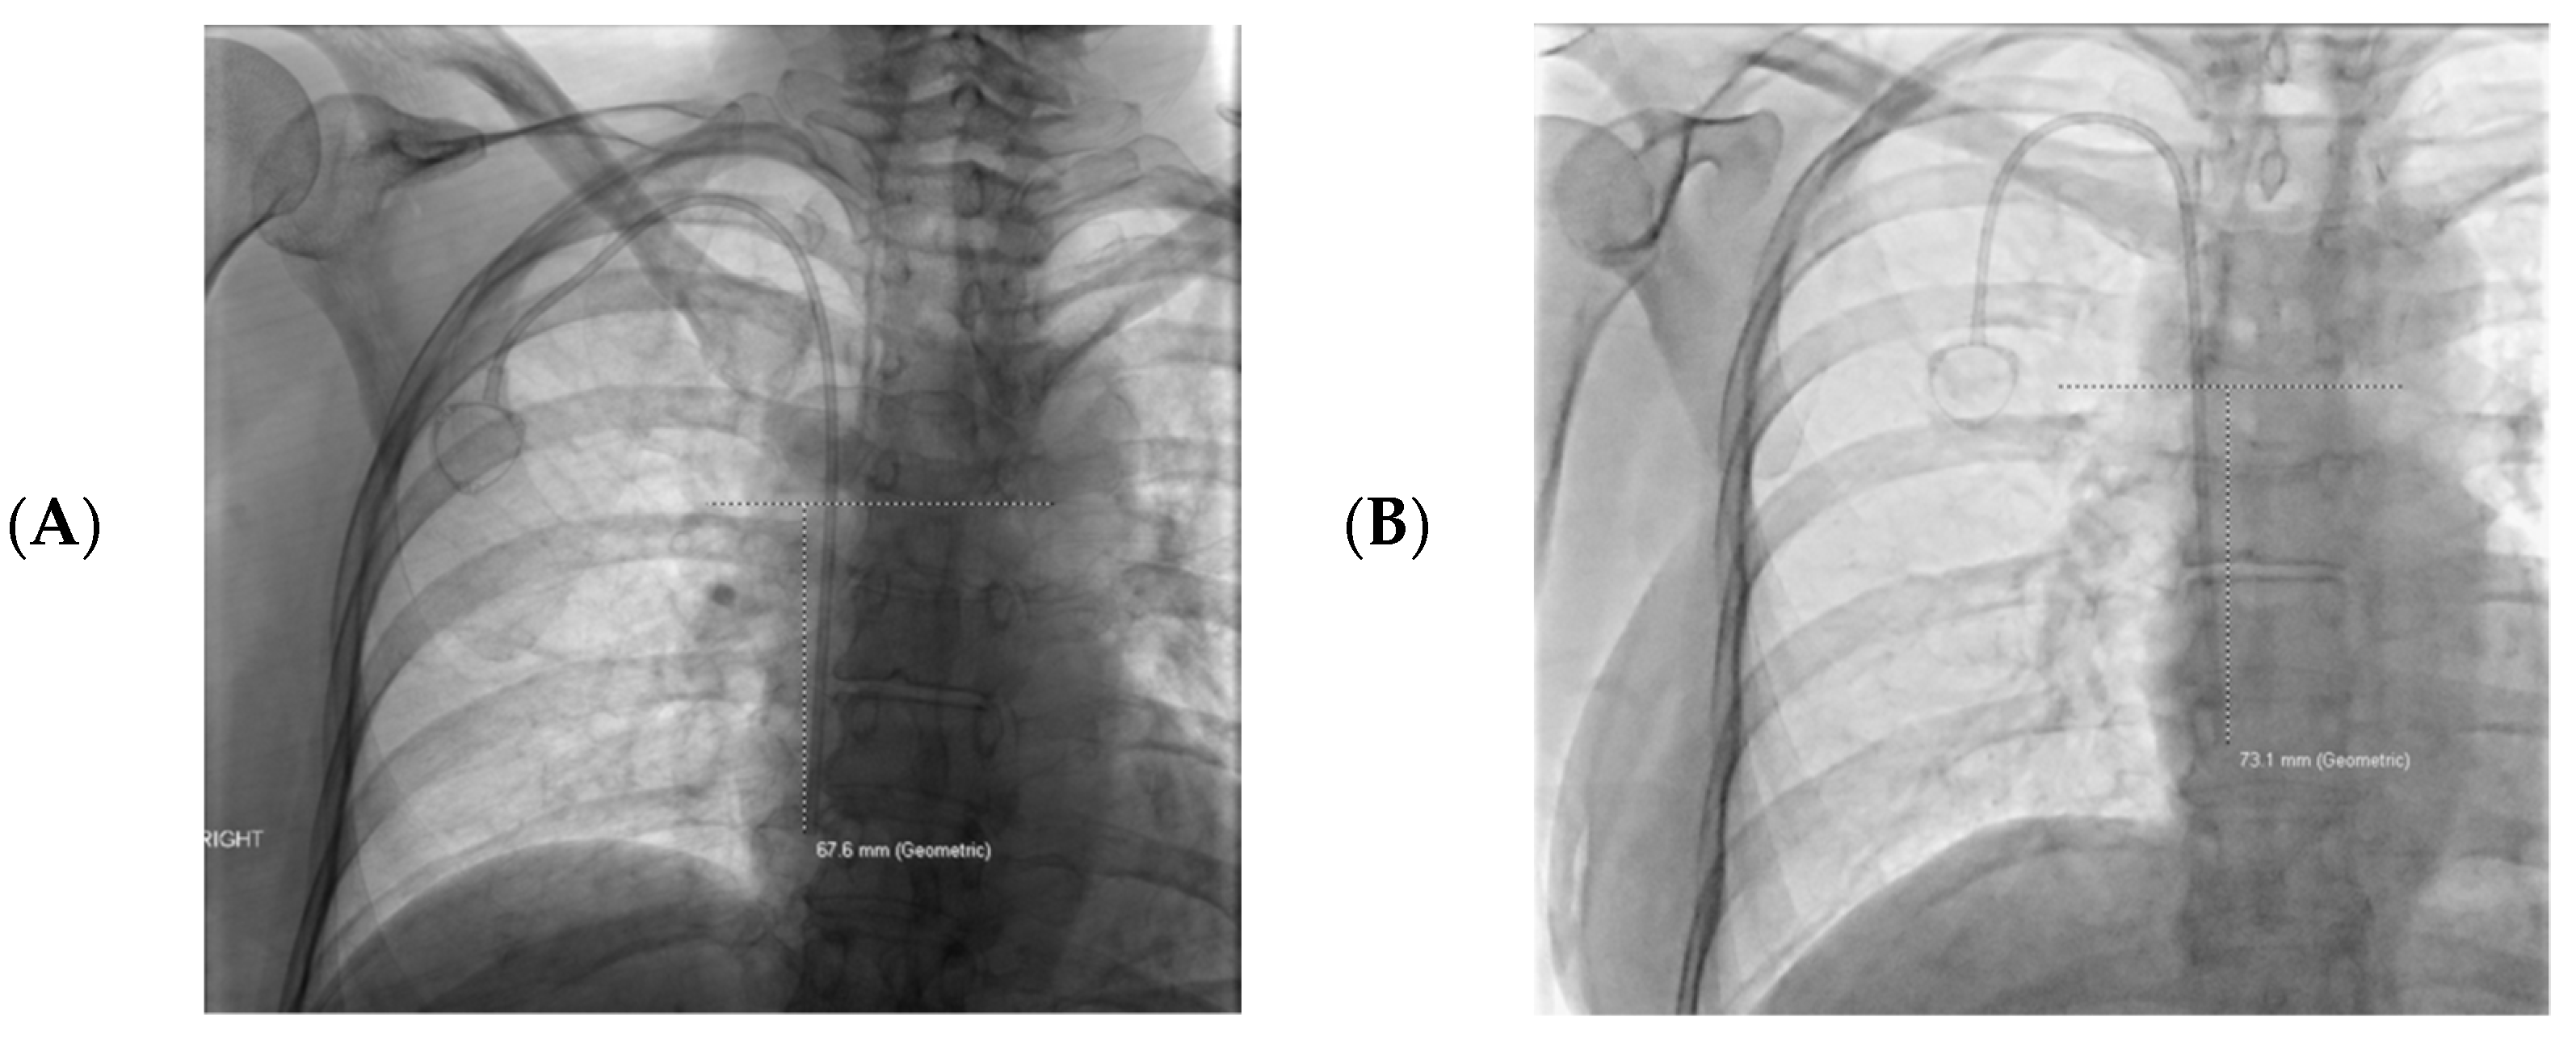

| Mean catheter tip migration | 3.2 cm cranially | 0.8 cm cranially | p = 0.000008 * |

| Catheter Dysfunction | 16 (32%) | 6 (4.7%) | Odds ratio for CVC dysfunction and >2 cm cranial tip migration: Odds ratio: 7.2 95% confidence interval 2.6–19.6 p = 0.0001 |

| >2 cm catheter tip cranial migration | 32 (64%) | 26 (20.5%) | Odds ratio for >2 cm of cranial catheter tip migration in left vs. right CVCs Odds ratio: 6.9 95% confidence interval 3.4–14.2 p < 0.0001 |